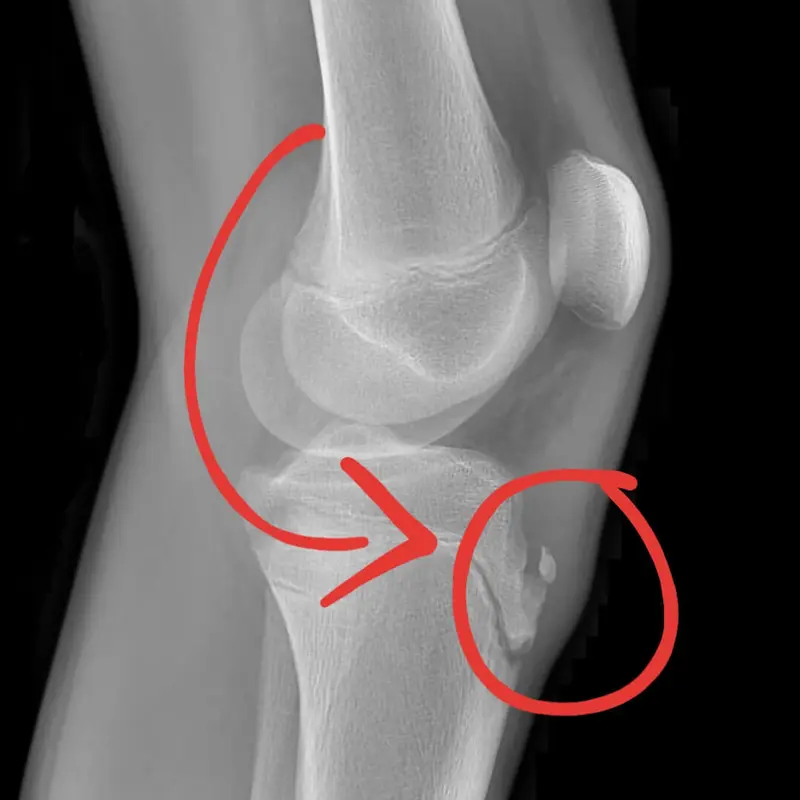

From radiopaedia.org

Image Icd 10 Code For Osgood Schlatter Disease Right Knee icd 10 code for juvenile osteochondrosis of tibia tubercle. Reimbursement claims with a date of service on or after october 1,. It is an inflammation of the area just below the knee where the tendon from. osgood schlatter disease, also known as osteochondrosis or traction apophysitis of the tibial tubercle, is a common cause of anterior knee. . Icd 10 Code For Osgood Schlatter Disease Right Knee.